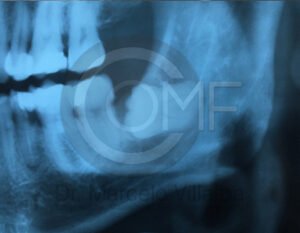

Antes de la extracción se realiza una valoración clínica y estudios de imagen, como radiografías panorámicas o tomografías, para conocer la posición del tercer molar, su relación con los nervios y planificar un procedimiento seguro y adecuado para cada paciente.

No es recomendable. Antes de extraer terceros molares es necesario realizar una valoración clínica y estudios de imagen para conocer la posición del diente, su relación con los nervios y el tipo de procedimiento más seguro para cada paciente.

Algunas extracciones simples de otras piezas dentales pueden ser realizadas por un odontólogo general; sin embargo, por la complejidad que presentan los terceros molares, o si se encuentran retenidos, impactados o cerca de estructuras importantes, se recomienda que el procedimiento sea realizado por un cirujano maxilofacial para mayor seguridad y control del tratamiento.